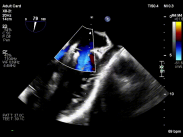

【图片7-9:术中定位、夹持过程及术后效果图】

术后评估显示,患者二尖瓣反流由极重度明显降低至中度以下,血流动力学改善,手术取得良好效果。